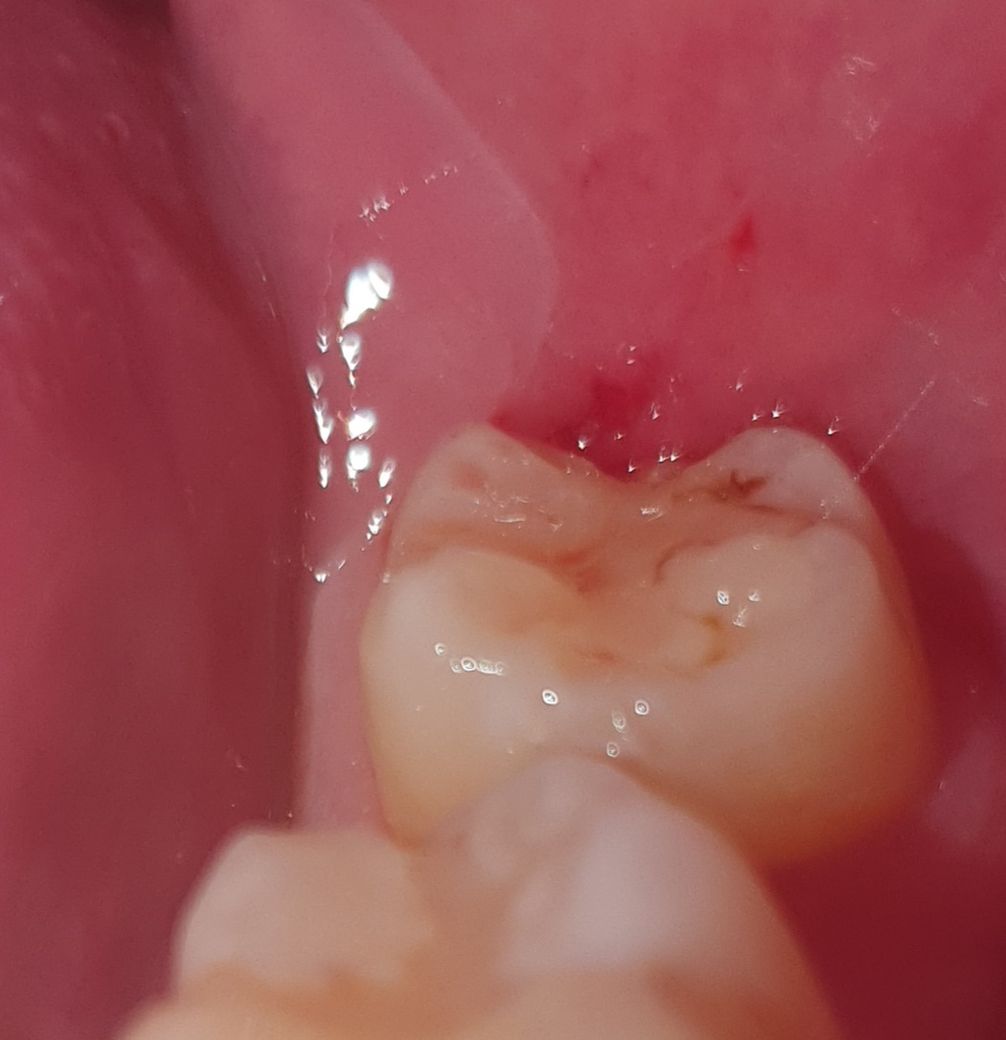

충치일까요? 충치라면 당장 치과에 가야할까요?

약 2달전에 교정 정기검진으로 치과를 갔다가 이번 5~6월쯤 다시 갈 예정인데

문듯 양치하다 거울을 봤더니 맨 안쪽 어금니가 이렇네요

아무래도 충치겠죠? 충치라면 나중에 치과를 갈때까지 치료를 미룰수 있을까요?

• 1번 째 사진

치아와 레진 사이에 충치 혹은 착색이 있어보이며 직접 검사를 해봐야 명확히 알 수 있겠습니다.

예전에 치료를 햇던곳 주변으로 착색 및 2차 충치가 생긴거 같습니다. 치과에 가셔서 검진을 받아보세요.

사진으로 봤을 경우에는 레진 충전물 주변으로 색상이 변화된 것으로 보입니다. 충치는 아닐 것으로 보이나 자세한 확인을 위해서 치과에서 진료를 받아보는 것을 권유드립니다.

현재 사진상 레진으로 떼운부위 주변으로 충치가 생긴것으로 보이며, 빠른시일내에 치과에 방문하여 상태를 확인하고 조기에 치료를 받길 권합니다.

기존에 떼운 재료의 변색, 착색 같습니다 만약 아무런 증상이 없다면 이차충치라는 근거는 엑스레이 찍어봐야 확인됩니다